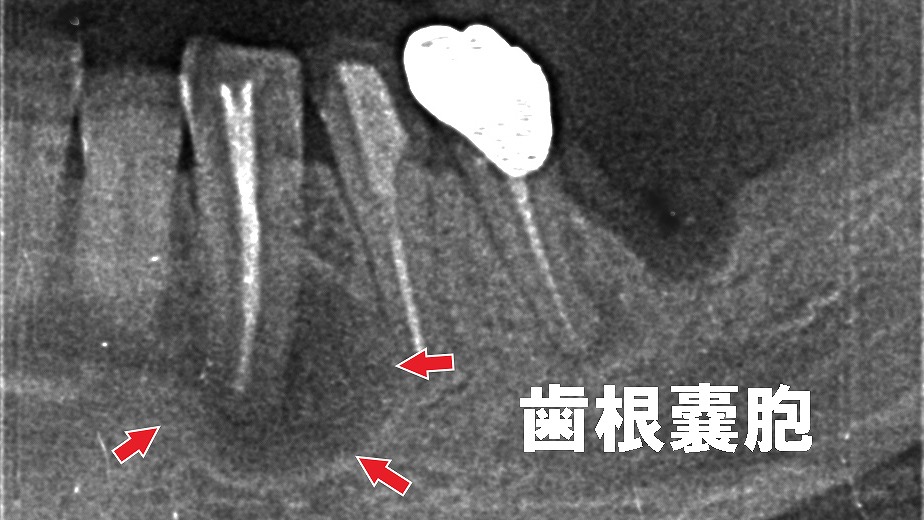

- 壊疽を放置すると、炎症が歯根外に広がり、歯根嚢胞を形成。

- さらに、歯ぐき表面に管(フィステル)ができ、膿が排出されます。

- フィステル形成により痛みは一時的に軽減しますが、感染は治っていないため抜本的な治療が必要です。